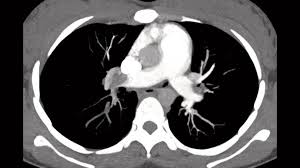

Pulmonary Embolism In Pregnancy - V Q Or Ctpa In Suspected Pe In Pregnancy Resus / Pulmonary embolism (pe) is a potentially fatal disease during pregnancy.. Ct pulmonary angiography was avoided in 32 to 65% of patients efficiency of algorithm highest during first trimester and lowest during third Pulmonary embolism is a complication of disturbance of coagulation which leads to thromboembolic disease. Pulmonary embolism during pregnancy is the most dreaded medical condition. All other patients had ct pulmonary angiogram (ctpa). In general, these procedures result in an embryonic or fetal exposure of less than 5 mgy, which is considered a safe dose in pregnancy.

All other patients had ct pulmonary angiogram (ctpa).